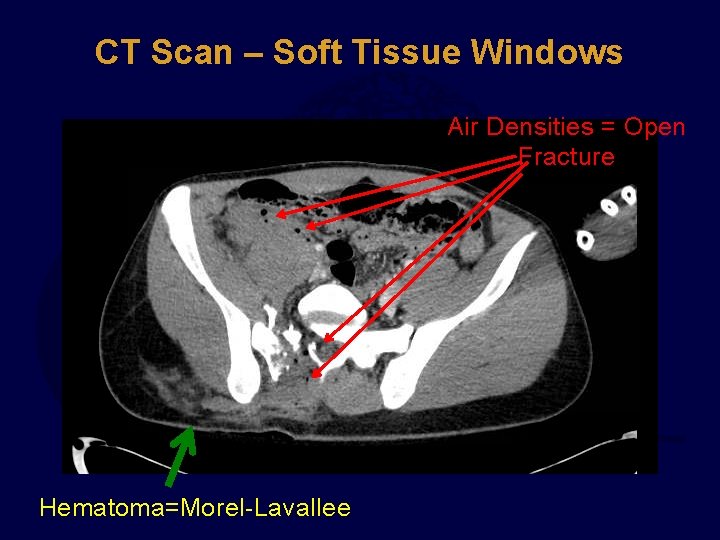

CT Scan Study SOFT TISSUE WINDOWS st 1 !!!! Look at bony injury last.

CT Scan – Soft Tissue Windows Air Densities = Open Fracture Hematoma=Morel-Lavallee